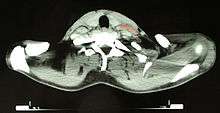

After Hodgkin lymphoma is diagnosed, a patient will be staged: that is, they will undergo a series of tests and procedures that will determine what areas of the body are affected. These procedures may include documentation of their histology, a physical examination, blood tests, chest X-ray radiographs, computed tomography (CT)/Positron emission tomography (PET)/magnetic resonance imaging (MRI) scans of the chest, abdomen and pelvis, and usually a bone marrow biopsy. Positron emission tomography (PET) scan is now used instead of the gallium scan for staging. On the PET scan, sites involved with lymphoma light up very brightly enabling accurate and reproducible imaging.[23] In the past, a lymphangiogram or surgical laparotomy (which involves opening the abdominal cavity and visually inspecting for tumors) were performed. Lymphangiograms or laparotomies are very rarely performed, having been supplanted by improvements in imaging with the CT scan and PET scan.